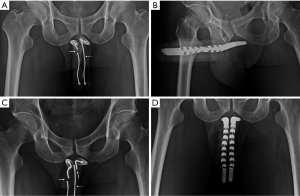

After the neurovascular bundle was protected, corporotomy was made on the CC (Figure 3A). Manual dexterity of handling the Hegar’s dilator was the major difference in those patients between the conventional and advanced group. During corporal dilatation, the tip of Hegar’s dilator was categorically directed medial-dorsally toward the distal ligament to avoid direct pressure on the region between the 5 and 7 o’clock position where the TA was composed of merely inner circular layer (Figure 3B,C). The intracavernosal pillars were kept lateral to both cylinders which have to be in the medial-dorsal positions, rooms one and two rather than rooms three and four (Figure 3D). After prosthesis was tailored to fit the CC, the corporotomy incision was closed with 6-0 nylon continuously with exact apposition of the TA and subsequently with interrupted sutures at each 2.5-cm interval for enhancement. The tubing system was fashioned and then the overlying fascia layers and skin were closed with 5-0 chromic suture layer by layer. The pain level was assessed with a 100-mm visual analog scale (VAS) at 2, 4, 8, 12 and 24 hours post surgery.

The model of prosthesis was recorded. Follow-up of patients including prosthesis survival, revision or end of patients’ life till August 2013. An anterior-posterior view of pelvis was undergone whenever patient revisited for either re-check or close observation. Proximal migration occurred merely in patients with semirigid prosthesis implant in 2 and 15 men to conventional and advanced group respectively (P=0.04) (Figure 4). Furthermore the prosthesis loss and revision surgery were analyzed and made when required (Figure 5). Six males concerning the penile length underwent penile elongation uneventfully (Figure 2A). Statistically student’s t-test or chi-squared test was either applied whenever necessary.